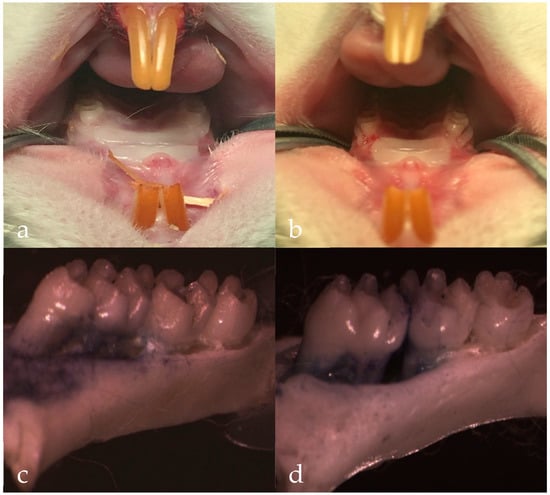

2.5. In Vivo Pharmacodynamics Studies

3.7. Statistical Analysis